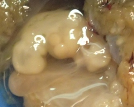

A Anatomia Patológica é uma especialidade médica laboratorial cujo objetivo principal é o diagnóstico morfológico através da observação de células e tecidos, de lesões médicas e cirúrgicas. Para além do diagnóstico, determina o prognóstico e permite orientar a terapêutica.

O SAP recebe e analisa todo o material histológico (biópsias e peças cirúrgicas), citológico (citologias aspirativas, esfoliativas, ginecológicas e não ginecológicas), realiza exames intraoperatórios e autópsias clínicas proveniente dos vários serviços do centro hospitalar. Tem ainda acordos com entidades externas nas áreas da Fetopatologia, Dermatopatologia e Imunocitoquímica.

Histopatologia

Observação Macro e Microscópica de material biológico retirado por:

- Biópsias(pequenas amostras resultantes de endoscopias digestivas, colonoscopias, broncoscopias, transplantes ou de pequenas cirurgias, por exemplo retalhos de pele);

- Peças cirúrgicas(resultantes da ressecção de órgãos como vesicula biliar, útero, estómago, próstata, tumores);

Técnica que, através de reações químicas, permite evidenciar determinados constituintes celulares, depósitos exógenos e microorganismos.